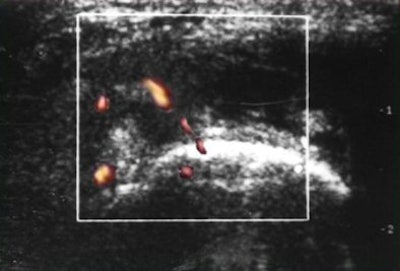

![]() |

| PDS shows markedly increased vascularity. |